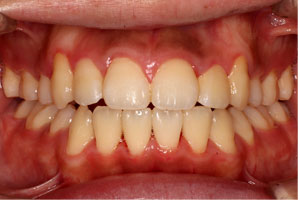

こちらの初診(男性)の患者さんは、開咬合 / 叢生歯列の症状がありました。

1期治療 8歳9ヶ月 2期治療 12歳4ヶ月から治療を開始し、1期治療 7ヶ月 2期治療 2年5ヶ月の間、スタンダードエッジワイズ法(与五沢エッジワイズシステム)を用い矯正治療を行いました。

| 症例分類 | 開咬合 / 叢生歯列 / 偏位咬合 | |||||||||||||||||||||||||||||||||||||||||||||||||||||||||||

| 12歳4ヶ月 | 15歳8ヶ月 | |